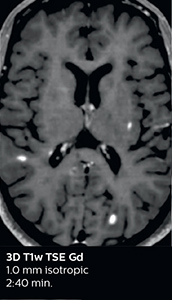

According to Dr. Savatovsky, Ingenia Elition has an impact in virtually all examinations. “We can either make the scanning faster compared to our older Ingenia 3.0T, or we save enough time so that we can add sequences we wouldn’t perform otherwise, or increase resolution. So, I think it has benefits for most of our patients.” “Some routine exams that we use every day have been shortened since we started using Elition. For example, we now use mostly a comprehensive stroke protocol (high b-value diffusion, fast 3D FLAIR, TOF, supra-aortic vessels angiography, SWIp, T1 post gad) that lasts 10 to 11 minutes, but our fast stroke protocol takes only 7 minutes. Our routine IAC needs about 10 minutes scan time and our comprehensive brain MS examination requires no longer than 13 minutes of scan time. Our ability to reduce acquisition times of most sequences helps to shorten total examination times, which in turn helps us to increase the number of patients we scan per day. “The main breakthrough for us was that Compressed SENSE and Multiband SENSE have allowed us to accelerate our examinations. Alternatively, we can invest the time gained in obtaining higher spatial resolution to see more details, or we can add additional sequences,” says Dr. Savatovsky. “That’s a big improvement from what we did before.”

A two year follow-up scan of a CPA meningioma using both Ingenia 3.0T without CS and Ingenia Elition 3.0T with Compressed SENSE allows for a nice comparison to demonstrate the protocol improvements achieved on the Elition: 3D FLAIR has a shortened scan time, improved SNR and still the same spatial resolution. BrainView (3D T1 TSE) has improved spatial resolution and SNR with shortened scan time. For 3D T2 Drive the spatial resolution has been improved. 3D THRIVE used to have an interpolated 0.8 mm slice thickness, but true thickness at 1.6 mm, so that axial slices displayed a decent quality, but reformats were suboptimal. Compressed SENSE is used on Elition to improve spatial resolution and reduce the non-interpolated slice thickness to allow smoothly reformatted images. Total scan time (adding SmartBrain and an additional b2000 diffusion) was 13:19 on Ingenia, and is now reduced to 10:42 on Ingenia Elition.

Ingenia Elition 3.0T with Compressed SENSE

3D FLAIR 1.0 x 1.0 x 1.0 mm* 2:50 min.

3D TSE T1w 1.0 x 1.0 x 1.0 mm* 2:10 min.

3D T2w Drive 0.7 x 0.7 x 0.7 mm* 2:52 min.

3D T1w THRIVE 0.7 x 0.7 x 0.8 mm* 1:30 min.

*true voxel size, without interpolation

This is an example of acute ischemic stroke with distal occlusion of the right posterior cerebral artery. Note the improved visibility of the ischemic territory on the diffusion weighted image with high b-value. The 3D FLAIR shows a distal PCA occlusion. The fast SWIp depicts the thrombus on the isolated second echo image. The total scan time (including SmartBrain, preparations and a fast 3D T1w TSE Gd) is 8:00 minutes.